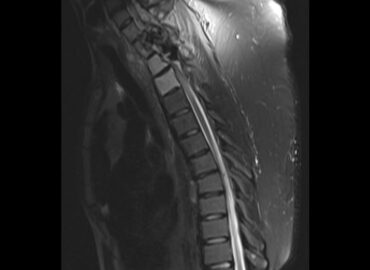

Paciente femenina de 25 años de edad. Ingresa por presentar masa dorsal gigante asociado a lesión cutánea hiperpigmentada y […]